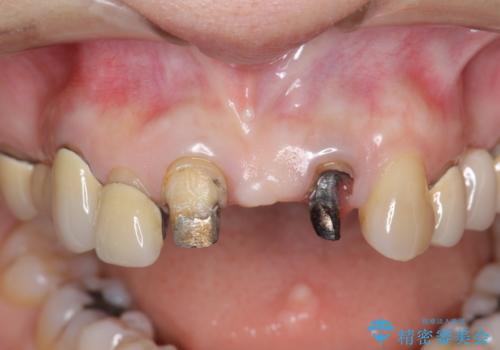

前歯ブリッジのやりかえ

- 前歯の審美障害、見た目の改善を希望され来院されました。

歯肉縁下カリエスも認められるため、挺出を行いセラミックブリッジを審美的に新製します。

- 47万円(仮歯×3・ファイバーコア×2・ジルコニアクラウン×3 歯の挺出)費用は治療当時の料金となります

虫歯が深くなった場合、挺出や歯周外科を行い歯周組織の状態を改善することでより安定した状態で予知性の高いセラミックブリッジを製作することが可能となります。